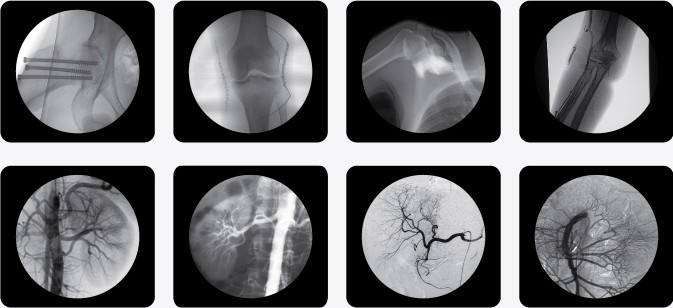

以下是南京C型臂X光機PLX7000C的產品參考圖,點擊產品圖下方紅色的產品名稱可以直接進入詳情頁面:

(普朗品牌產品--C型臂X光機PLX7000C)